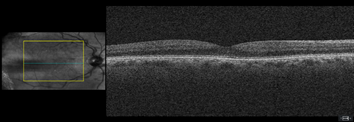

Dilated fundus examination revealed relatively normal fundus with cup-to-disc (C/D) ratio of 0.30 round OD (Figure 1A). The fundus photo of the left eye showed a pale posterior pole with swollen optic nerve head and macular cherry spot (Figure 1B). Ocular coherent tomography (OCT) macular cube scans showed a representative slice of normal retinal layers through the macula OD (Figure 2A), and a pigmented epithelial detachment and disrupted retinal layers extending temporally from the optic nerve head (ONH) OS (Figure 2B). Additionally, Figure 3 and Figure 4 showed the OCT optic disc cube 200x200 scan with swollen ONH OS, and OCT macular cube 512x128 scan with detached retinal layers OS, respectively.

Figure 2A a slice of OCT macular cube showing normal retinal layers OD.

Figure 2B a slice of OCT macular cube showing pigmented epithelial detachment, and disrupted retinal layers OS.